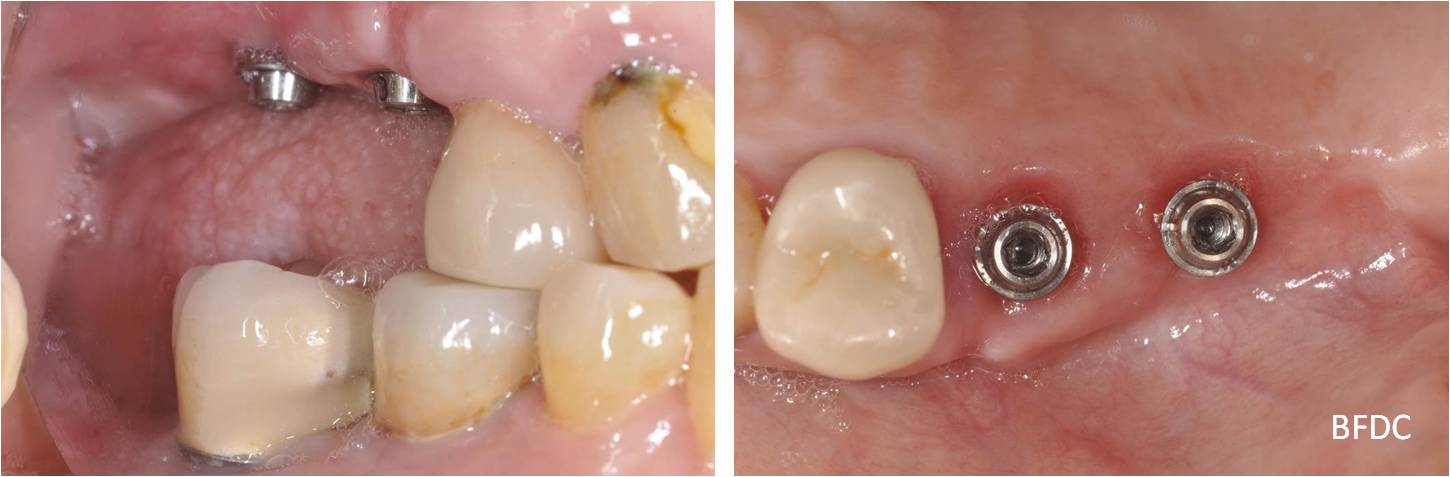

植體植入

植體二段式假牙口內套件